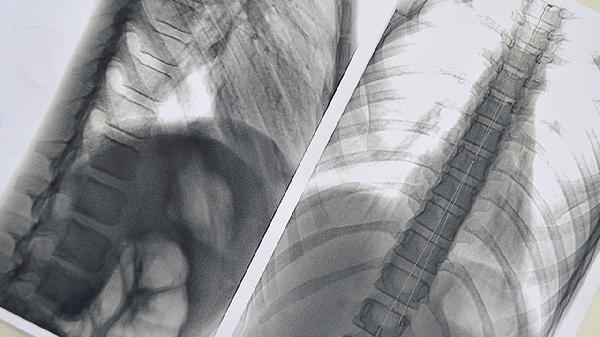

使用治療器期間應(yīng)定期進(jìn)行胸廓CT三維重建評估,若矯正進(jìn)度停滯超過3個(gè)月或出現(xiàn)胸骨生長板損傷需終止使用。配合呼吸訓(xùn)練可增強(qiáng)肋間肌力量,游泳等伸展運(yùn)動(dòng)有助于提升矯正效果。治療結(jié)束后仍需穿戴保持器3-6個(gè)月防止復(fù)發(fā),日常需注意保持正確坐姿避免駝背,青春期患者需監(jiān)測生長發(fā)育對矯形效果的影響。